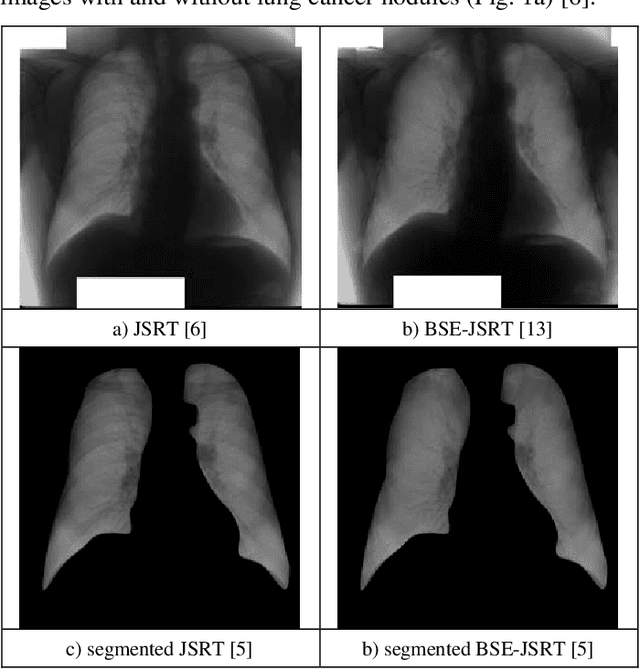

Abstract:Efficiency of some dimensionality reduction techniques, like lung segmentation, bone shadow exclusion, and t-distributed stochastic neighbor embedding (t-SNE) for exclusion of outliers, is estimated for analysis of chest X-ray (CXR) 2D images by deep learning approach to help radiologists identify marks of lung cancer in CXR. Training and validation of the simple convolutional neural network (CNN) was performed on the open JSRT dataset (dataset #01), the JSRT after bone shadow exclusion - BSE-JSRT (dataset #02), JSRT after lung segmentation (dataset #03), BSE-JSRT after lung segmentation (dataset #04), and segmented BSE-JSRT after exclusion of outliers by t-SNE method (dataset #05). The results demonstrate that the pre-processed dataset obtained after lung segmentation, bone shadow exclusion, and filtering out the outliers by t-SNE (dataset #05) demonstrates the highest training rate and best accuracy in comparison to the other pre-processed datasets.

Abstract:The recent progress of computing, machine learning, and especially deep learning, for image recognition brings a meaningful effect for automatic detection of various diseases from chest X-ray images (CXRs). Here efficiency of lung segmentation and bone shadow exclusion techniques is demonstrated for analysis of 2D CXRs by deep learning approach to help radiologists identify suspicious lesions and nodules in lung cancer patients. Training and validation was performed on the original JSRT dataset (dataset #01), BSE-JSRT dataset, i.e. the same JSRT dataset, but without clavicle and rib shadows (dataset #02), original JSRT dataset after segmentation (dataset #03), and BSE-JSRT dataset after segmentation (dataset #04). The results demonstrate the high efficiency and usefulness of the considered pre-processing techniques in the simplified configuration even. The pre-processed dataset without bones (dataset #02) demonstrates the much better accuracy and loss results in comparison to the other pre-processed datasets after lung segmentation (datasets #02 and #03).